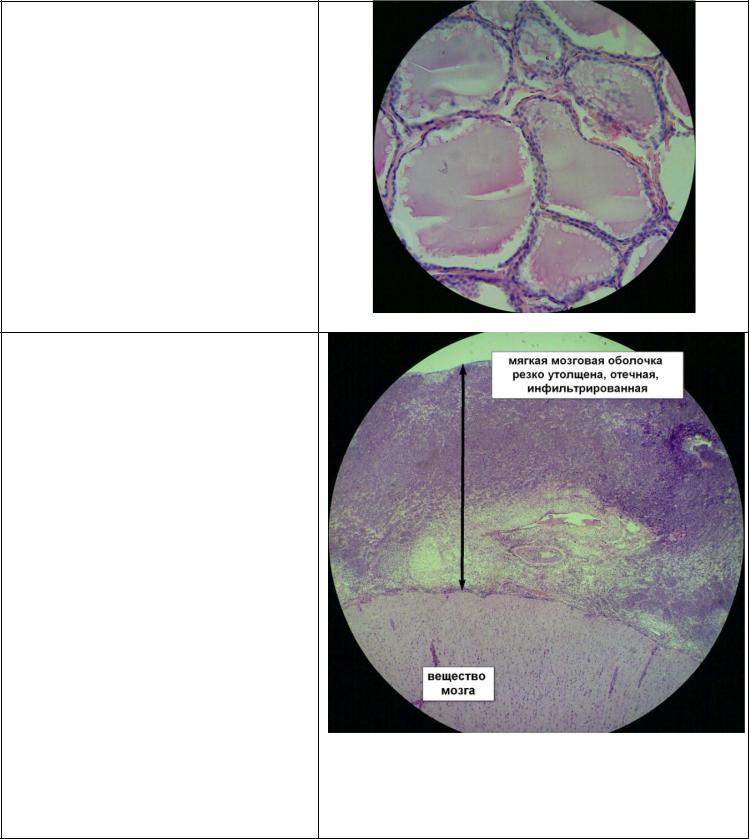

33.менингококковый гнойный менингит

Менингококковый менингит - одна из генерализованных клинических форм менингококковой инфекции - вызывается менингококком и характеризуется острым началом, появлением общемозговыхи менингеальных симптомов, а также признаками токсемии и бактериемии.

Морфологические изменения при гнойном менингококковом менингите

обнаруживаются в мягкой мозговой оболочке, в веществе мозга, эпендиме мозговых желудочкови субэпендимальнойобласти. В

начальной фазе воспаления преимущественно поражается мягкая мозговая оболочка и процессносит серозно-гнойный характер, а в дальнейшем - гнойный и гнойно-фибринозный.

По мере прогрессирования

патологического процесса поражается и Инфильтрация сегментоядерными лейкоцитами

вещество головного мозга в результате воздействия на ткань мозга как самих менингококков, так и их токсинов.